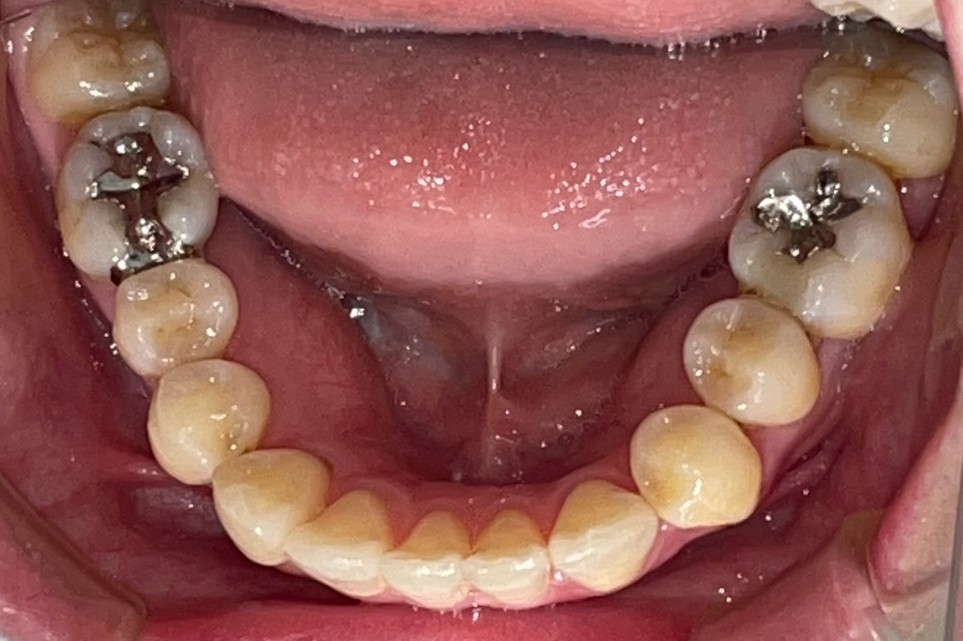

Before

After

矯正の種類 / SmileTRU

年齢・性別 / 30代女性

主訴  /  下顎前歯部の歯並びがガタガタしている(叢生症例)

治療期間 / 8ヶ月

費用 / 模型・3Dデータ診断 35,000円(税別)

上顎マウスピース14枚 308,000円(税別)下顎マウスピース8枚 176,000円(税別)

※マウスピース交換時別途調節料3,000円(税別)

副作用 / 口内炎・歯の移動に伴う痛み・知覚過敏 ※数日で収まる場合が多いです

リスク / 後戻り防止の為、夜のみマウスピースで保定を指示